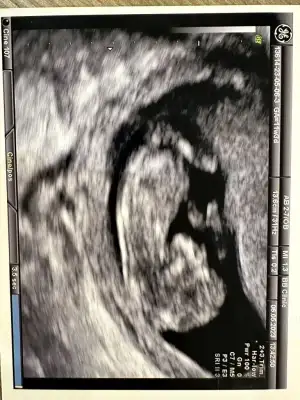

11+3’ten selamlar ❤️❤️ bugün kontrolümüz vardı, geriye yolunda dedi doktor, ikiz olduğu için de tarama testlerinin geçerli olmayacağını söyledi. Fetal DNA yaptırmamı önerdi. 12. Haftayı tamamlayıp öyle kan vereceğim, ikiz olduğu için her yer çalışmıyormuş, hem de miniklerin DNA sı biraz daha çoğalsın dedi. Ultrason görüntülerimizi de paylaşıyorum. Miniklerin cinsiyetleri ile ilgili tahmininiz var mı 🥰🥰🙏😘